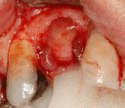

Soft tissue (gingiva) reconstruction

The gingiva surrounding a tooth has a 2–3 mm band of bright pink, very strong attached mucosa, then a darker, larger area of unattached mucosa that folds into the cheeks. When replacing a tooth with an implant, a band of strong, attached gingiva is needed to keep the implant healthy in the long-term. This is especially important with implants because the blood supply is more precarious in the gingiva surrounding an implant, and is theoretically more susceptible to injury because of a longer attachment to the implant than on a tooth (a longer biologic width).[28](pp629–633)

When an adequate band of attached tissue is absent, it can be recreated with a soft tissue graft. There are four methods that can be used to transplant soft tissue. A roll of tissue adjacent to an implant (referred to as a palatal roll) can be moved towards the lip (buccal), gingiva from the palate can be transplanted, deeper connective tissue from the palate can be tranplanted or, when a larger piece of tissue is needed, a finger of tissue based on a blood vessel in the palate (called a vascularized interpositional periosteal-connective tissue (VIP-CT) flap) can be repositioned to the area.[25](pp113–188)

Additionally, for an implant to look esthetic, a band of full, plump gingiva is needed to fill in the space on either side of implant. The most common soft tissue complication is called a black-triangle, where the papilla (the small triangular piece of tissue between two teeth) shrinks back and leaves a triangular void between the implant and the adjacent teeth. Dentists can only expect 2–4 mm of papilla height over the underlying bone. A black triangle can be expected if the distance between where the teeth touch and bone is any greater.[18](pp81–84)